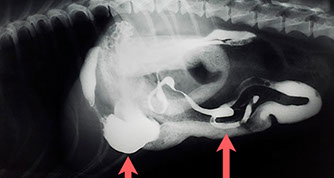

Harnsteine in Harnblase und Harnröhre (Katheter stößt auf die Steine)